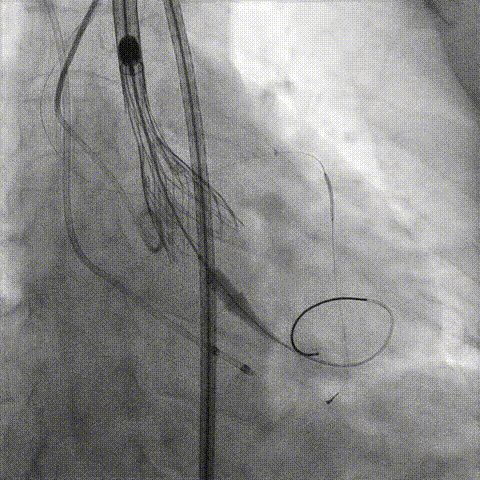

冠脉造影

手术策略和器械选择

预置Telescope™导引延长导管及导丝保护左冠,

18mm球囊预扩张再次评估冠脉闭塞风险。

Telescope™+Runthrough

18mm*40mm 预扩张

预埋 Resolute Integrity 3.5*26mm

再次评估左冠开口